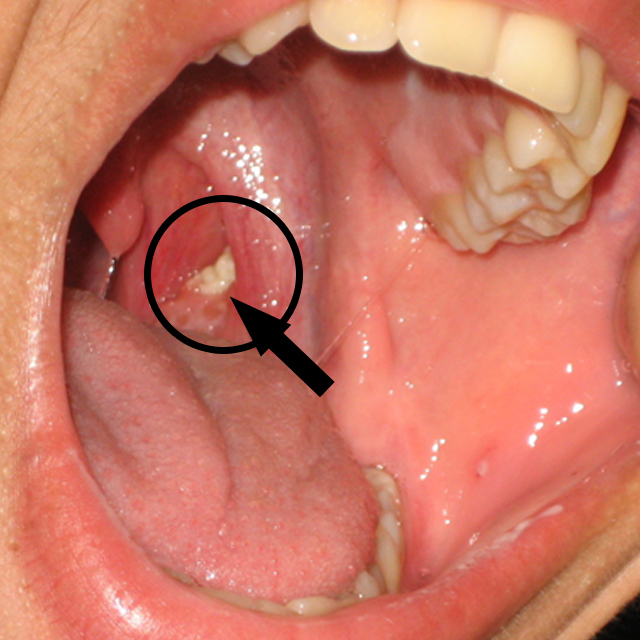

실제로 이것을 육안으로 보기에는 입을 크게 벌리고 편도선 근처를 밝게 비춰야 확인할 수 있지만 실제로 본인의 구취가 심한 것을 모르고 생활하는 분은 오랫동안 방치되어 있습니다.